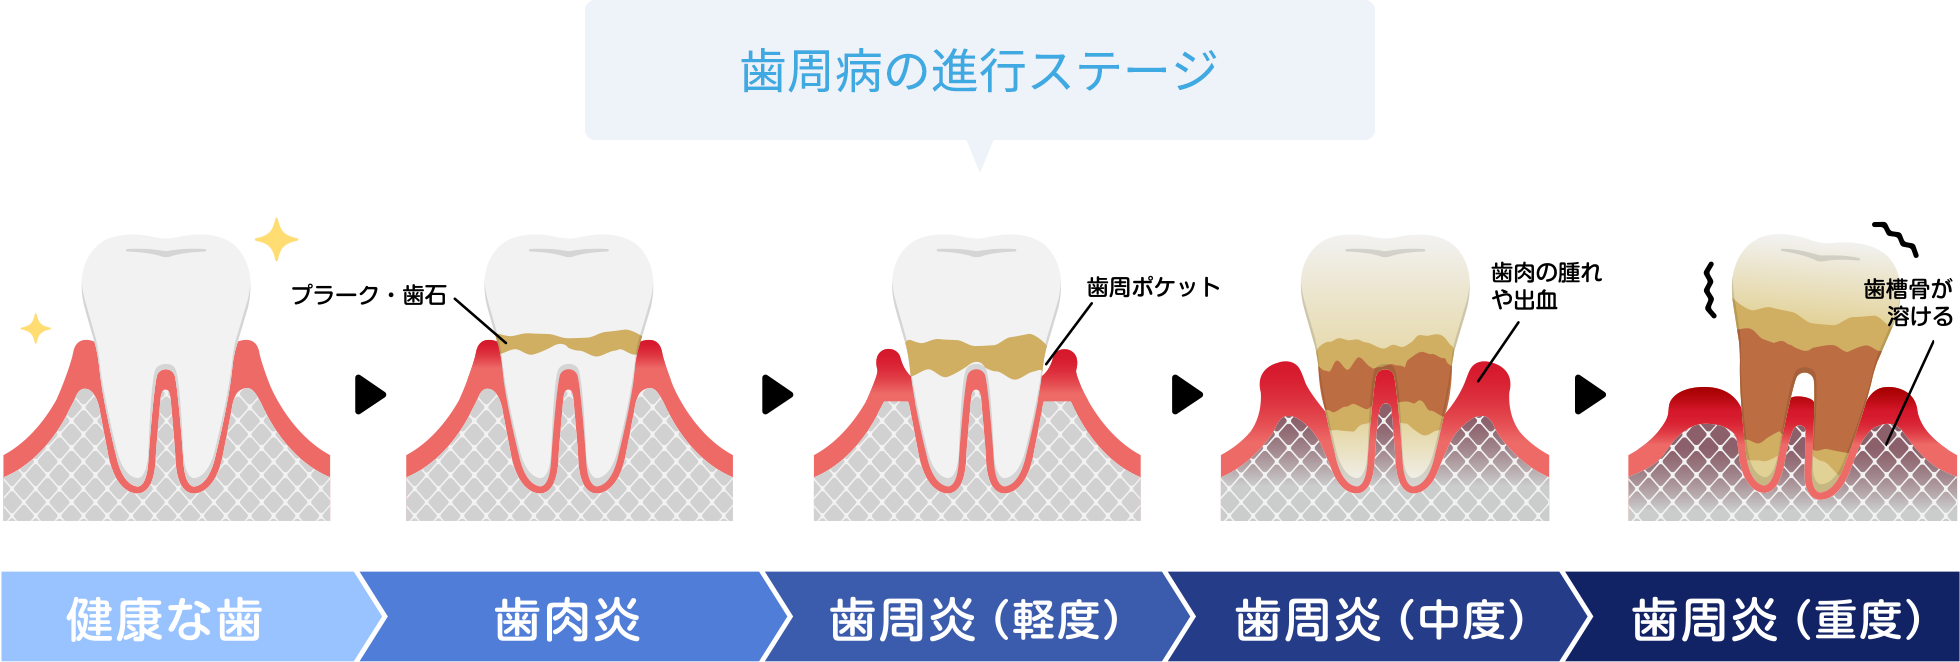

歯周組織が壊されてしまう病気

細菌の感染によって引き起こされる炎症性疾患です。歯と歯肉の間(歯周ポケット)の清掃が行き届かないことで細菌が繁殖して感染します。症状が重くなると、歯を支える歯槽骨が溶けてしまい、最終的には歯が抜けてしまうこともあります。

歯周病はその進行度によって、治療が異なりますが、口腔内の細菌の繁殖を抑えるためのメンテナンスによる口腔管理が治療の中心です。重度の場合や経過観察で回復が見られない場合には、歯茎を切開し歯槽骨に付着した汚れやダメージを受けた歯肉などを除去するフラップ手術を行います。

横スクロールで確認いただけます。